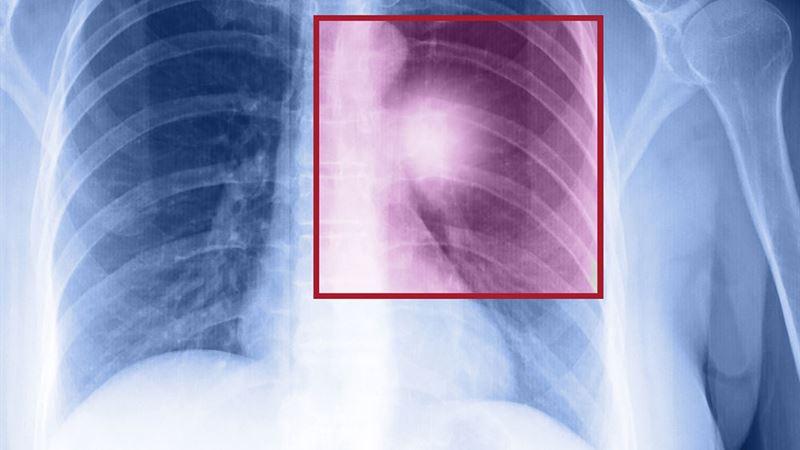

Lung cancer, especially when it reaches an advanced metastatic stage, can manifest through a combination of respiratory and systemic symptoms. Recognizing these early indicators can significantly impact prognosis and treatment outcomes.

The presentation of metastatic lung cancer varies depending on the extent of disease spread and the specific locations involved. The metastasis typically targets vital organs such as the bones, brain, and liver, leading to distinct clinical features.